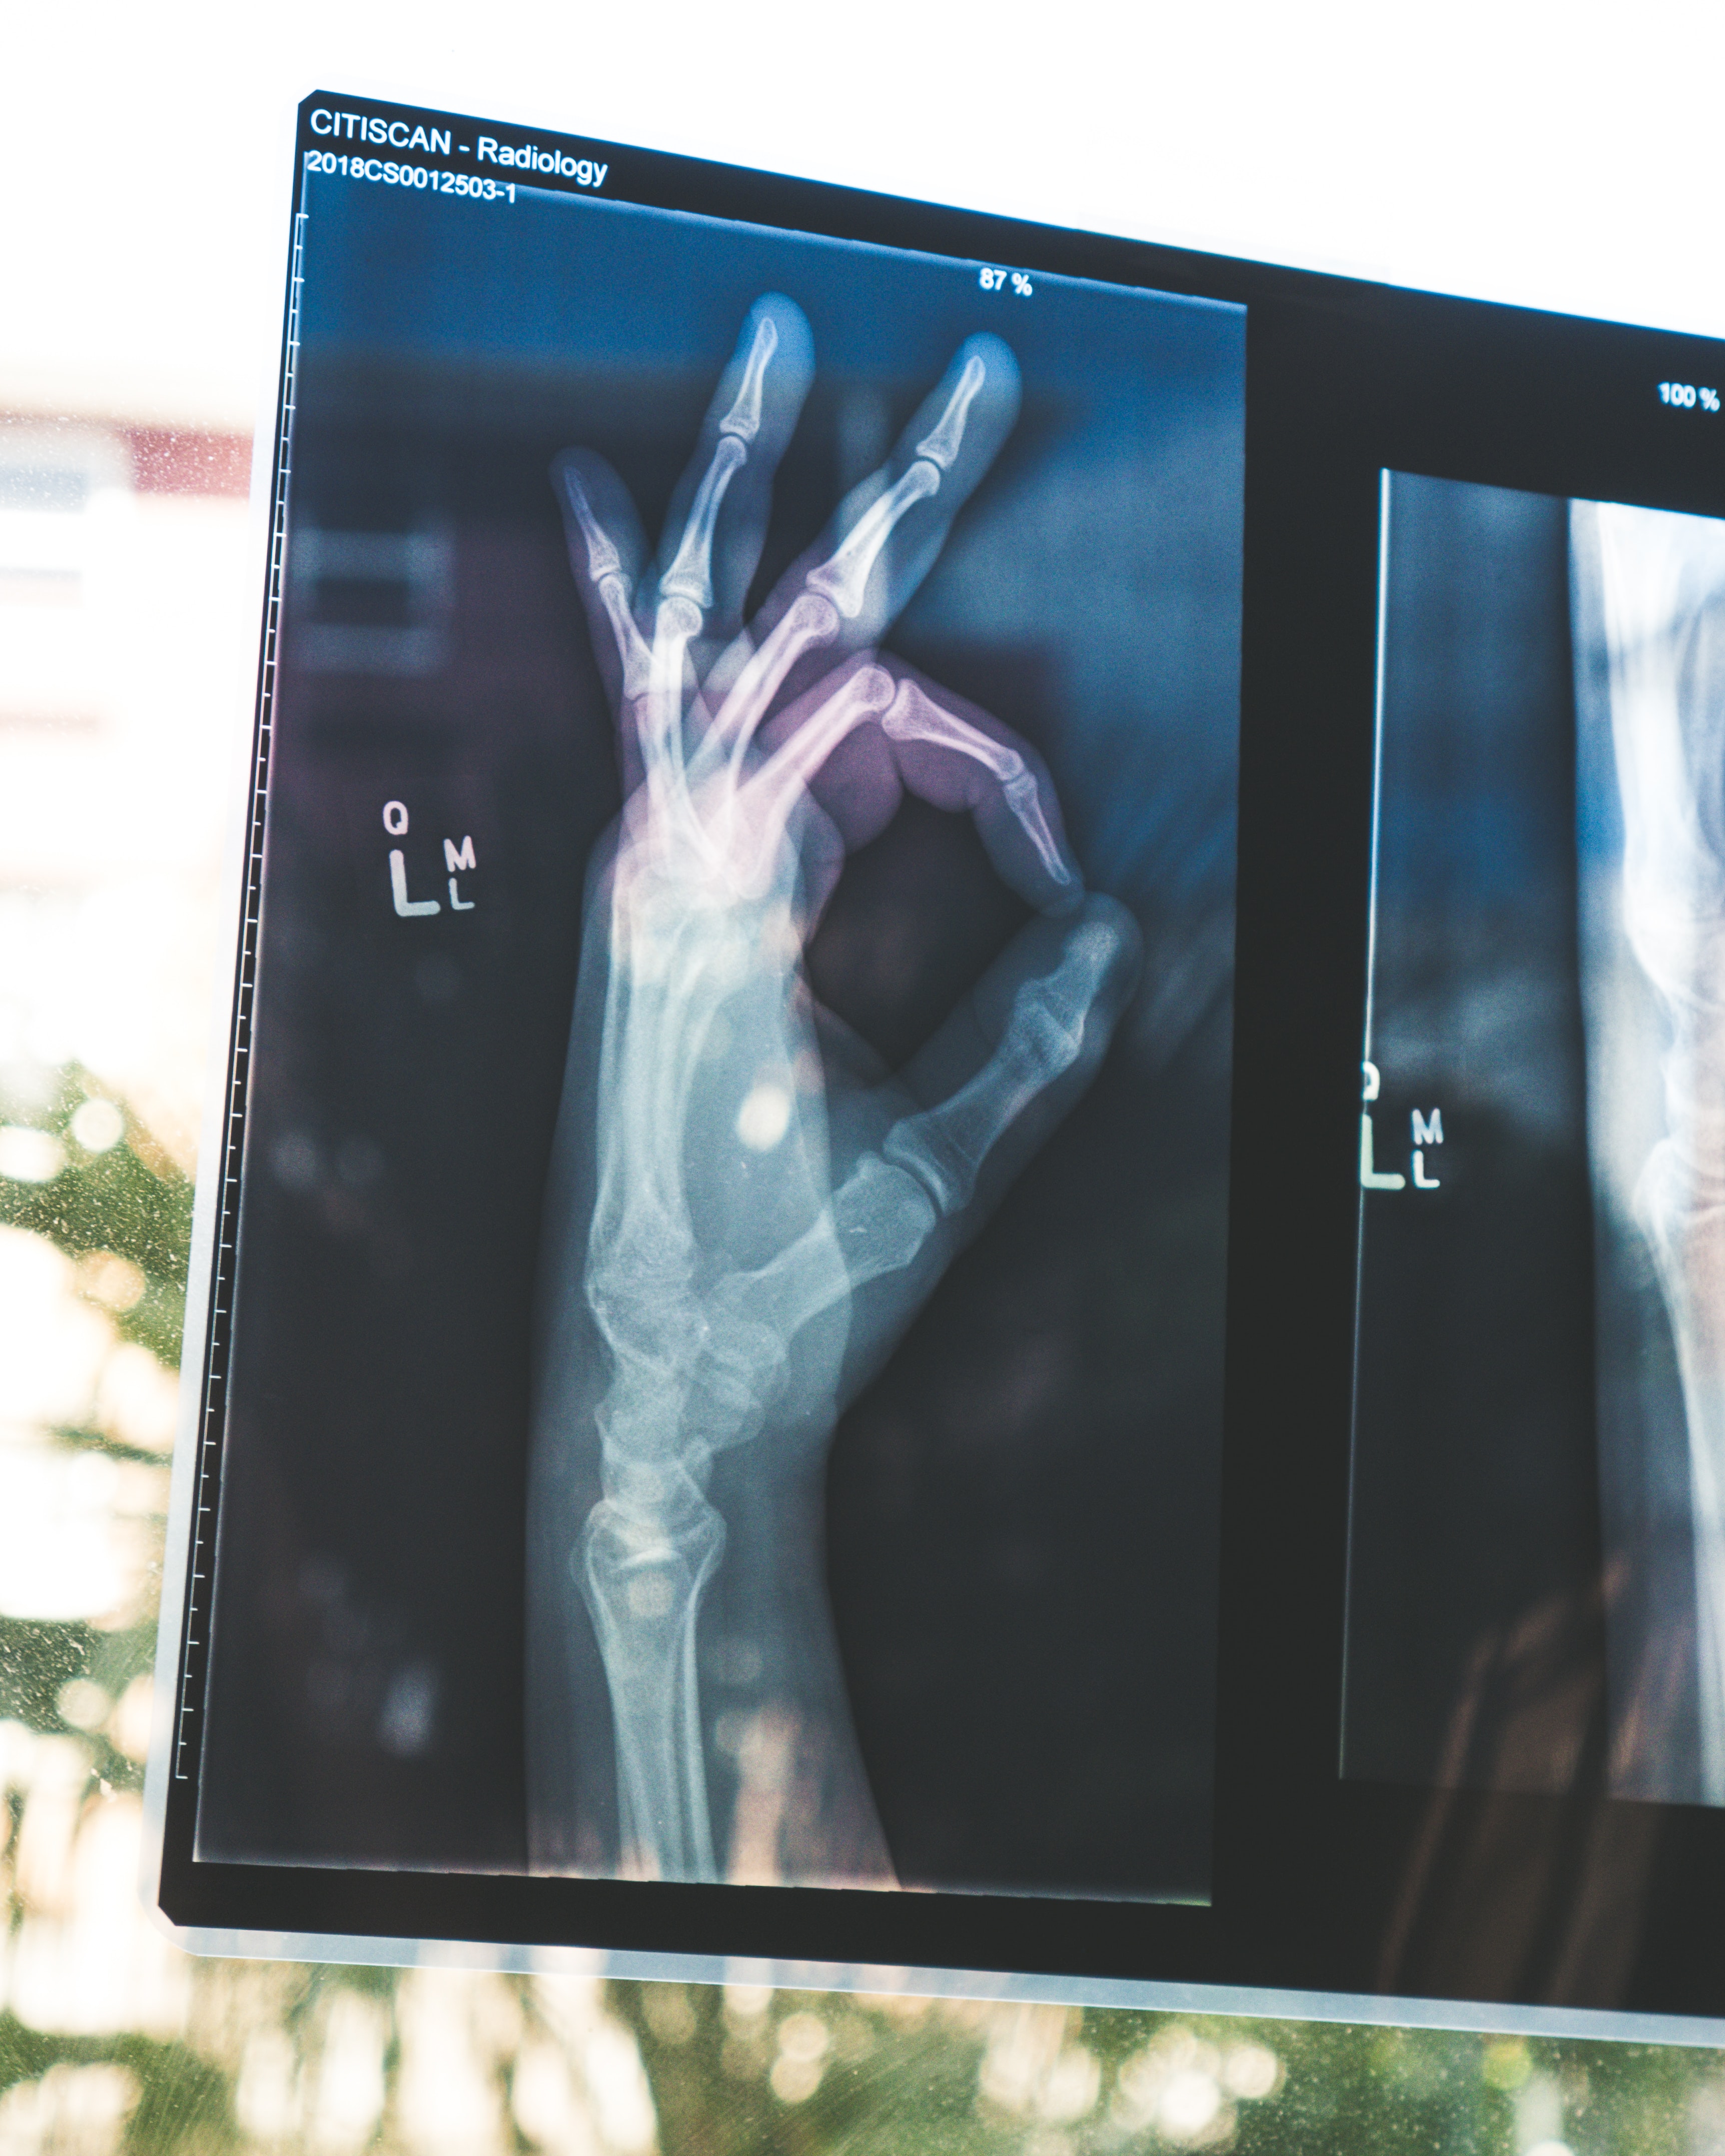

그럼 반대로 비타민D가 부족하면 어떤 일이 생길까. 앞전에 언급한 대로 골다공증,골연화증,구루병,각종 만성질환, 면역체 계약화, 피부 습진 등을 유발할 수 있다. 골다공증, 골연화증은 말 그대로 뼈가 약해진다는 이야기이다. 그만큼 뼈가 부러지기 쉽다는 거다. 구루병은 성장판이 닫히기 전에 뼈에 문제가 생겨 나타나는는 병. 이 구루병 역시 비타민 D이 부족하면 발생할 수 있는 질병이다. 만성피로와 수면장애 역시 발생할 수 있다. 또한 우울한 기분을 느낄수 있다.